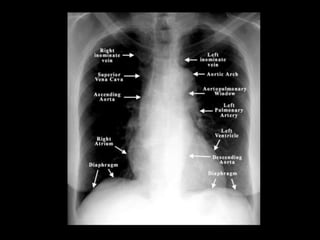

The document discusses the anatomy of the chest x-ray and CT scan by describing the lobes of the lungs and their locations. It also mentions the heart, mediastinum, hilum, and ribs. Several axial, coronal, and sagittal CT images are included with labels pointing out structures like the trachea, bronchi, lobes of the lungs, and fissures. In summary, the document provides an overview of lung and chest anatomy as seen on x-rays and CT scans through text descriptions and labeled medical images.